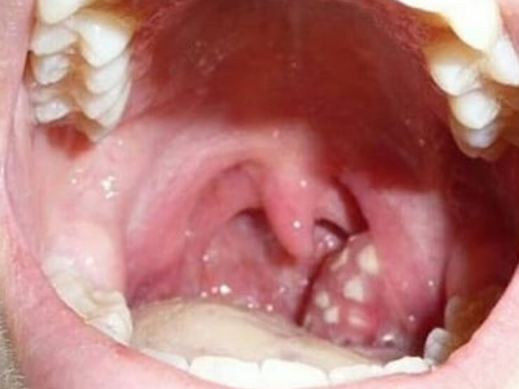

편도에 생긴 편도 결석. 악취의 원인이 됩니다.

결론부터 말씀드리면, 대부분의 편도 결석은 입을 벌리면 편도에 붙어 있기 때문에 발견하기 쉽습니다. 하지만 결석이 때때로 보이지 않을 수 있어요. 보이지 않는다고 해서 결석이 아예 없는 것은 아니에요. 편도의 뒷부분이나 주름 속에 숨어서 있는 경우에는 보이지 않기 때문입니다. 결석이 보이지 않더라도 엑스레이나 CT를 찍었을 때 발견됩니다.

손전등을 들고 거울 앞에 섭니다. 편도선이 잘 보이도록 입을 벌립니다. 편도가 잘 안보일 수도 있는데 혀를 내밀고 높은 소리를 내면 목구멍이 열리고 혀가 바닥으로 내려갑니다. 예를 들어 미성으로 하~~~~~하면 편도가 쉽게 관찰됩니다.편도선에 빛을 비추고 각 편도선에 흰색 반점이나 노란 덩어리가 있는지 철저히 검사해보세요.